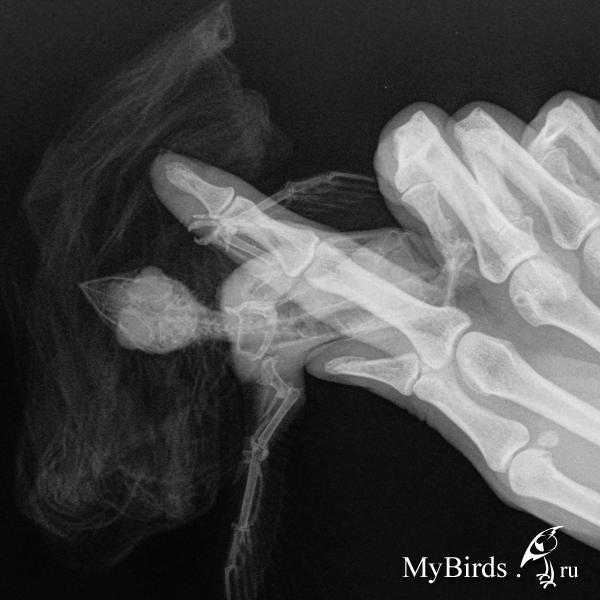

Врач сказал, вывих плеча, когда трогаешь чувствуется как там все смещается (((, и перелом лучевой кости, со смещением,наложил крестообразнуе повязку и крыло примотал к телу иначе сустав будет смещаться. Посмотрите пожалуйста снимки и подскажете что делать ??????

post-61846-1436378449_thumb.jpg post-61846-1436378467_thumb.jpg